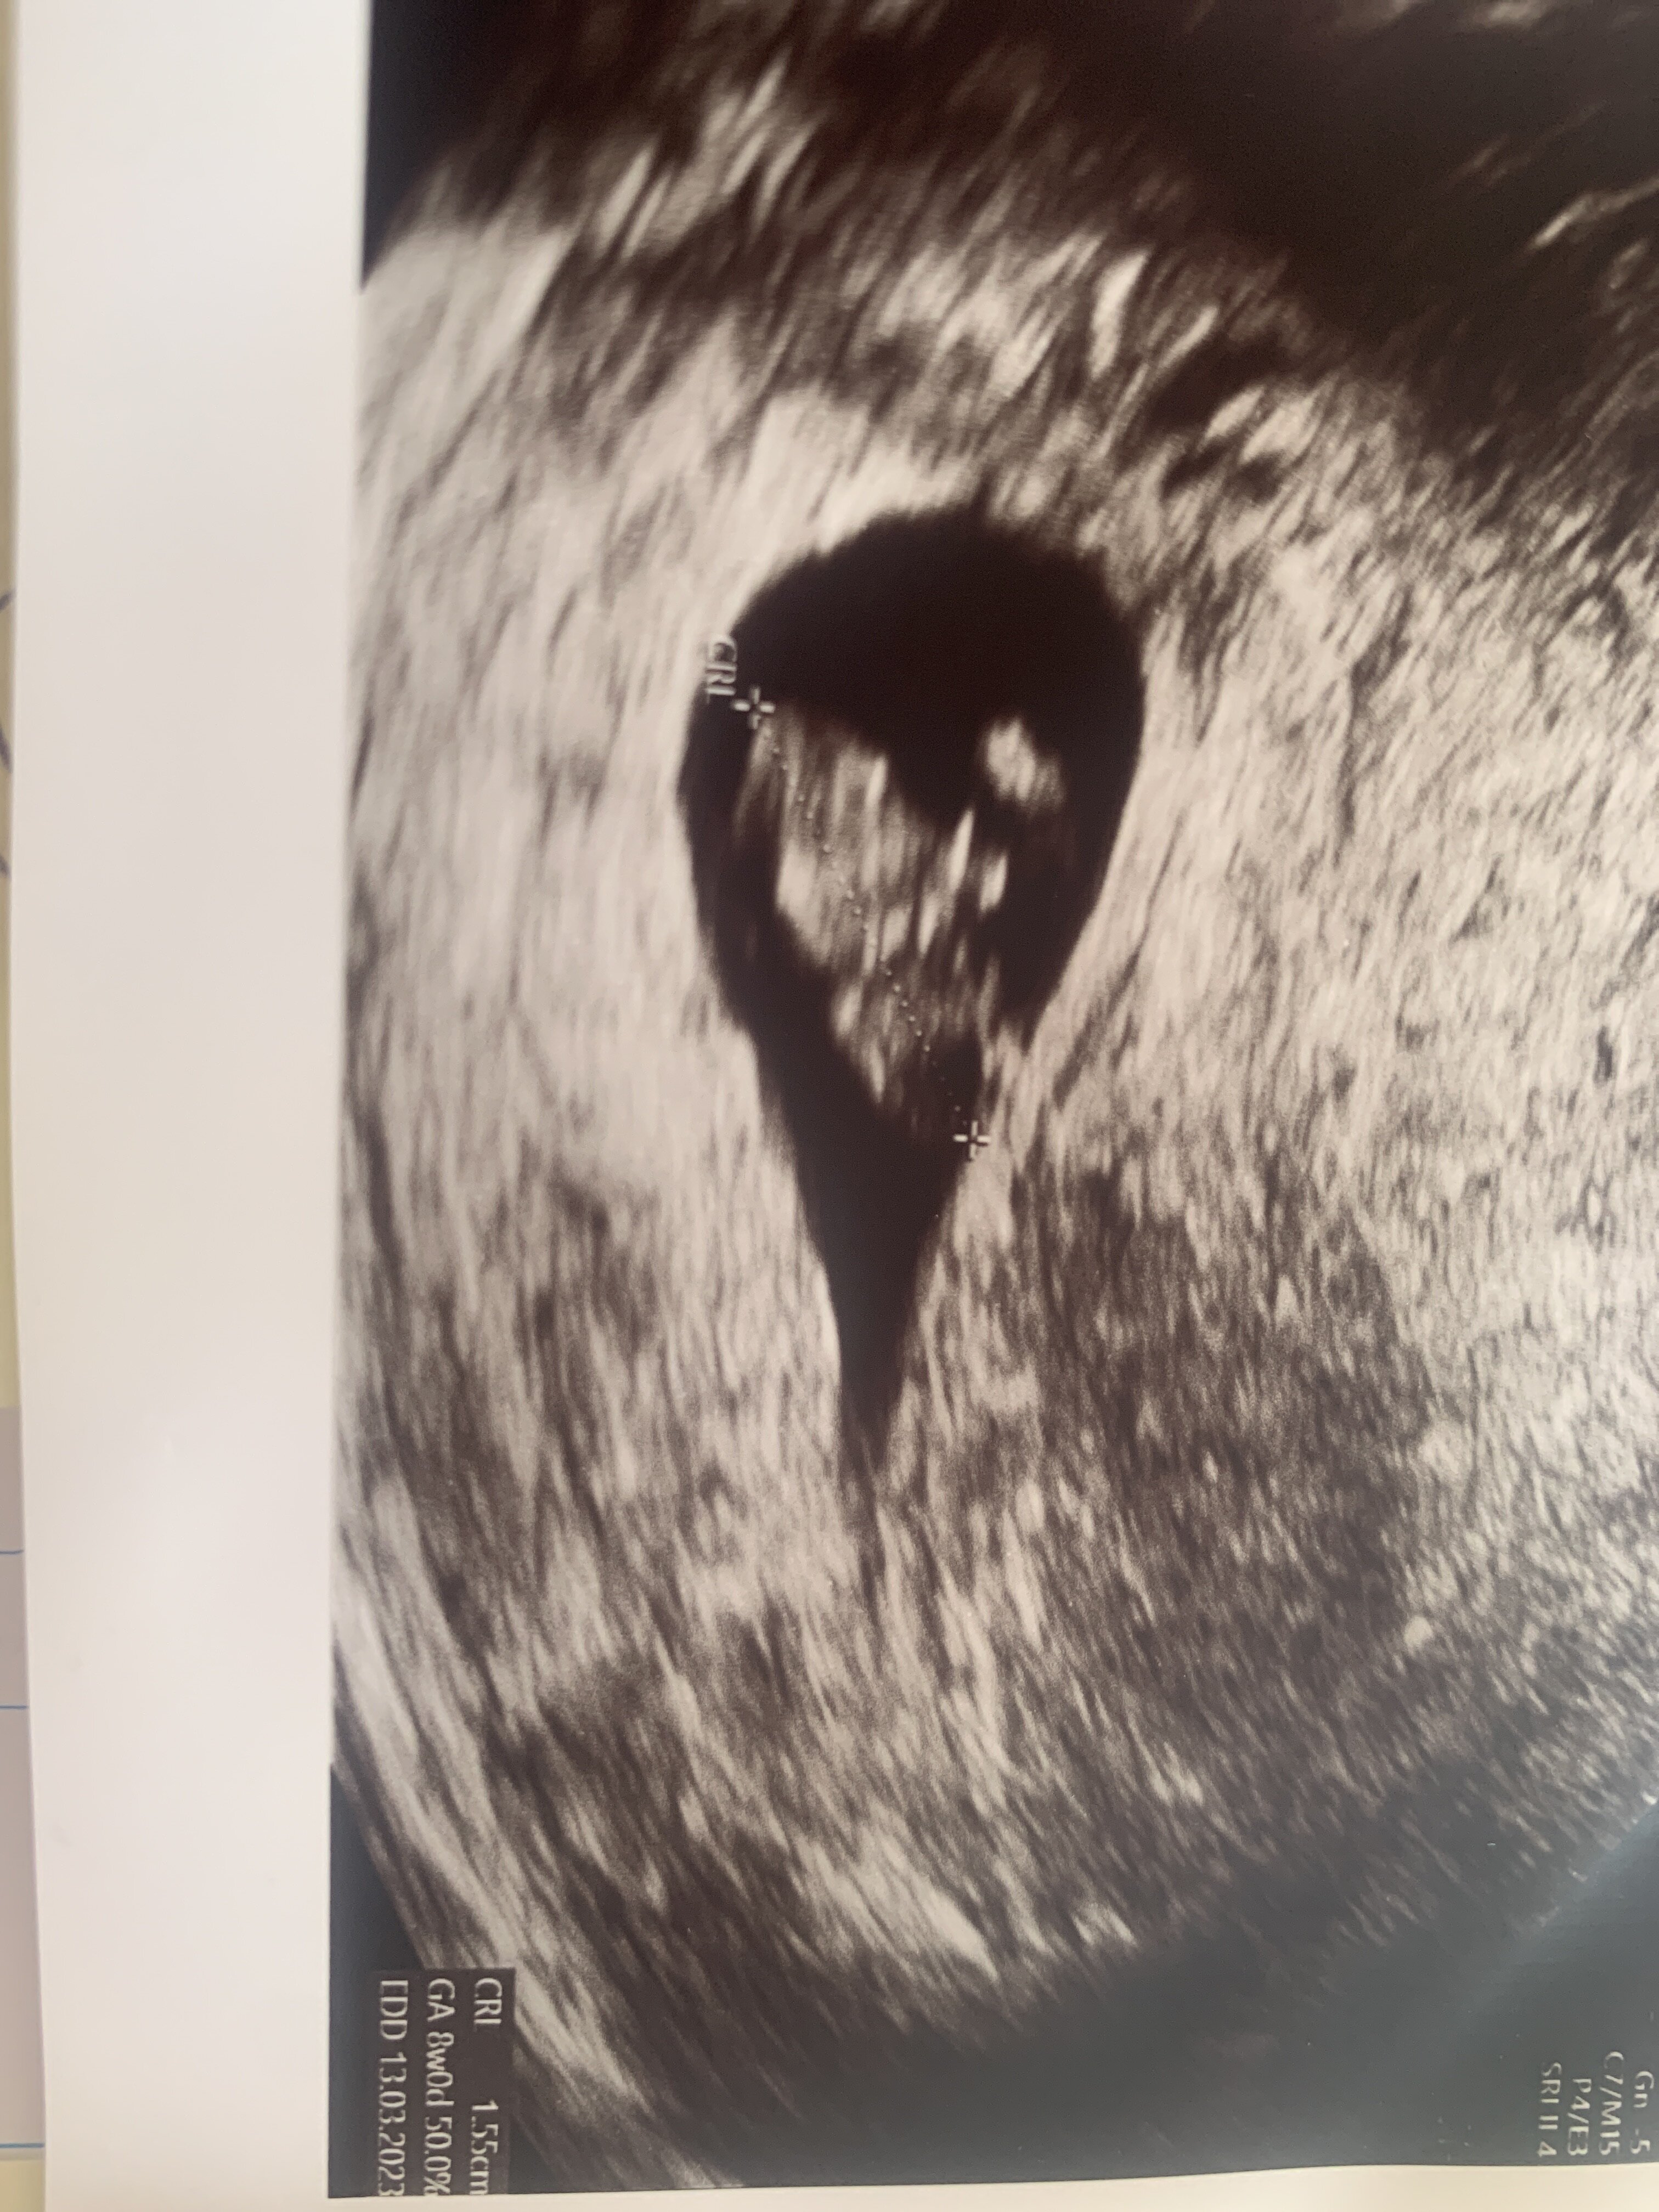

Hejka Kochane! Z całego serduszka dziękuję za wszystkie mocno zaciśnięte kciukasy. Przydały się jak nie wiem ❤️ Prawie zemdlalam siadając na fotel. Okazało się, że owszem cialko żółte nie jest najmniejsze, ale Pani Doktor (a jej akurat ufam) powiedziała że wielkość ok- czasem jest skorelowana z wadami genetycznymi, ale to kompletnie nie jest etap na którym cokolwiek można wyrokować. Czasem nie znaczy zawsze. Genetyje będziemy oceniać dopiero później jak już wszelkie struktury będą widoczne. Narazie powiedziała zeby to cialko zolte w ogóle z głowy wyrzucic- obraz ciałka ciążowego, zarodka, kształt wszystkiego wygląda naprawdę bardzo ładnie. Nie ma też już śladów plamien, krwawienia, szyjka macicy wygląda ok i struktura brzucha w badaniu manualnym tez wygląda ok 🥰 powiedziała że nie raz już widziała większe cialko i to o niczym nie świadczyło tak długo jak jego obraz u obraz całej reszty był w porządku... taki kamień z serca że aż mi zły poleciały 😭 powiedziała że na tym etapie wszystko wygląda ksiazkowo- maluch rośnie zgodnie z planem, serduszko biję jak dzwon. Powiedziała tez że większość poronień uwarunkowanych dysfunkcja ciałka żółtego dzieje się do 9tc (my już go zaczelismy) wiec ona jest dobrej myśli 🥰 Nasz mały człowieczek ma 2,33 cm i srduszko bije 176/min ❤️ Partner aż po prostu w skowronkach jak zobaczył wreszcie naszego małego fasolka 🥰 Przesyłam wam tysiące uścisków i podziękowania za wszelkie słowa otuchy i kciuki ❤️ jesteście najlepsze! Ja teraz staram się nastawiać pozytywnie 😊 i 3mam się tego ze musi być dobrze! I wierzę że badania genetyczne tez wyjdą ok ❤️

śliczne zdjęcie :) lekarze Wam dają? ja nie mam ani jednego z poprzedniej ciąży

Załączniki

• image.jpg

image.jpg

1,4 MB · Wyświetleń: 76